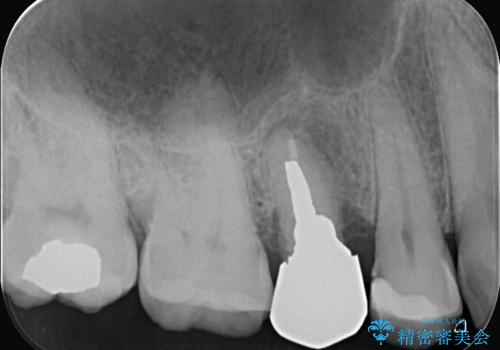

- 「歯茎にニキビみたいのが出来て歯が揺れている」を主訴に来院された患者様です。

右上5番が根尖性歯周炎と歯周病が同時に併発しており、骨が大きく溶け、歯の動揺も著しかったため保存困難と判断をし抜歯してインプラントで治療を行いました。

右上4番は虫歯になっていたので、虫歯を除去後、セラッミクインレーで治療を行いました。